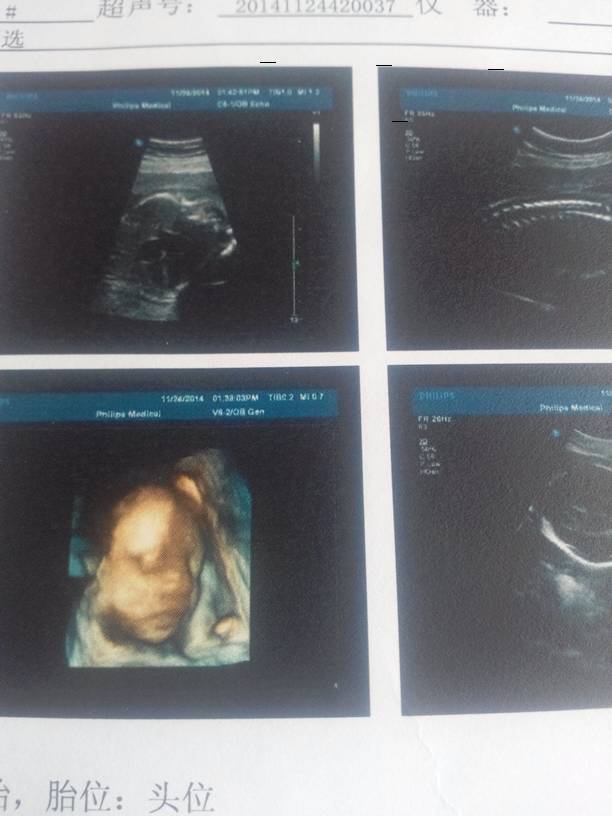

四维彩超,小家伙现在四斤了,胖胖的!哈哈 点击展开 亲亲宝贝喽 2014-11-27 20:41 为您推荐: 其他回答 根据你的情况,如果现在胎儿的发育和状态非常正常的情况下,没有必要担心的。平时需要注意休息,加强营养,定期到医院进行复查的。 shenglongxiao 2014-11-28 10:22 相关问题 刚在医院回来,检查得一切正常,小家伙现在有1斤八两了 开心 我四个月去检查称重45 六个月去做四维彩超称重48 两个月我才重了六斤 会不会有点太不正常 我家是双胞胎宝宝提前1月刨腹产现在已经五个月了妹妹才9斤多是吃奶粉有没有好的建议能长胖胖的